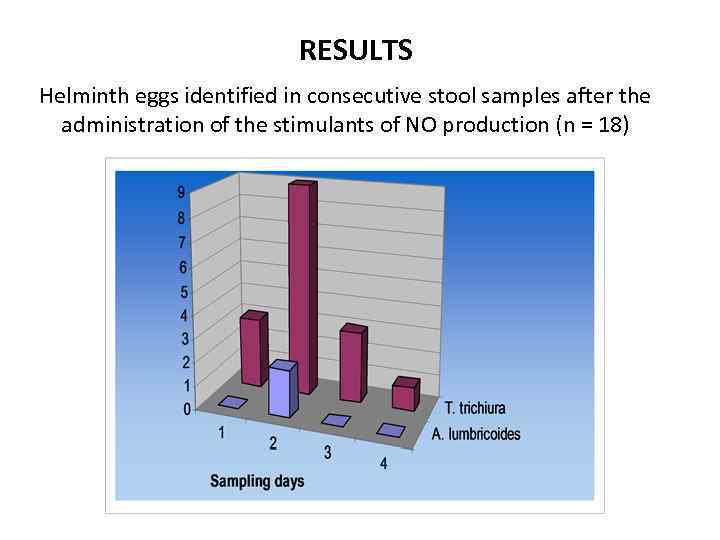

STUDY DESIGN To those 112 patients who had not responded to mebendazole, the following nutritional products were administered: -L-Arginine, 500 mg two or three times a day -Ionic Magnesium, 1 ml (15 mg) three times a day -Ionic Zinc, 1 ml (1, 8 mg) three times a day for 3 weeks. After completing the supplementation, stool microscopy was performed during 4 consecutive days.

RESULTS Helminth eggs identified in consecutive stool samples after the administration of the stimulants of NO production (n = 18)